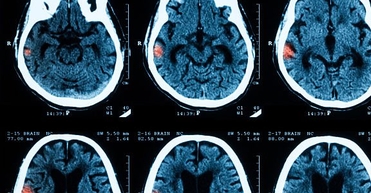

МРТ головного мозга при эпилептических синдромах